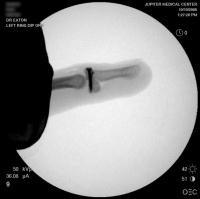

Intraoperative fluoros: The injury, reconstruction through a bayonette exposure, stable reduction.